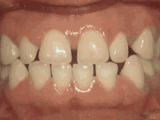

第二種---

前牙移位,因為有牙齒缺失,導(dǎo)致相鄰牙齒開始沒有秩序的左右移動,經(jīng)過矯正后是變成這樣的~